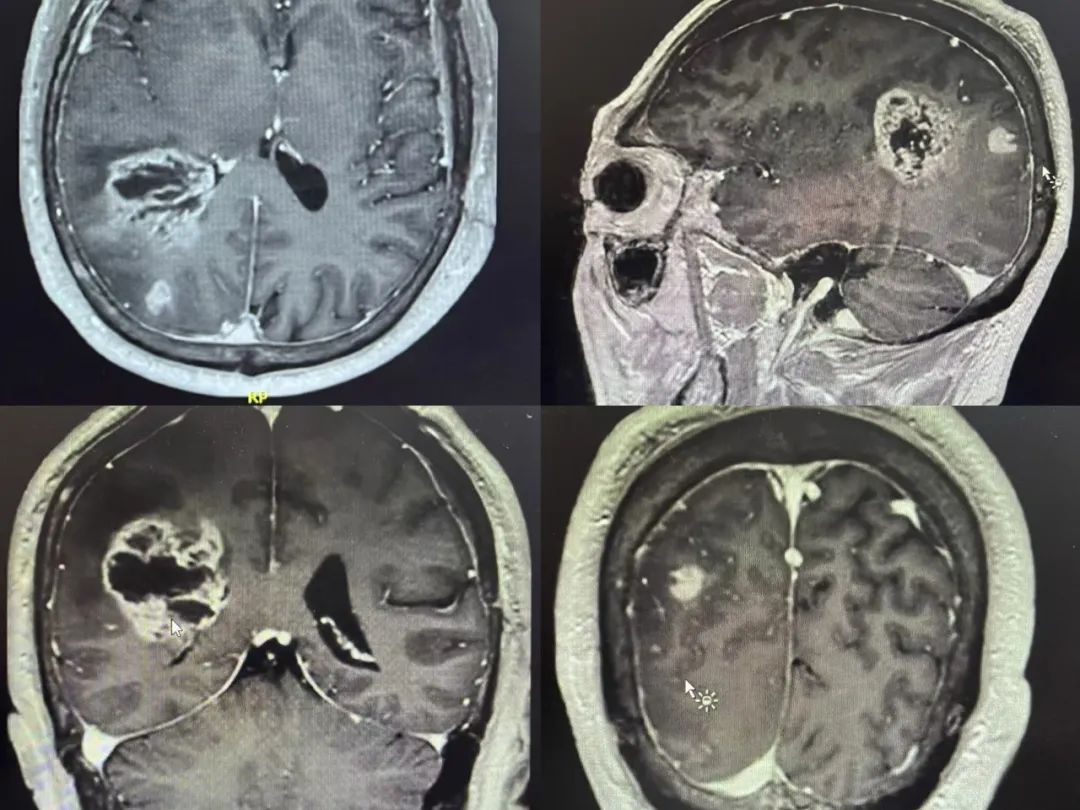

病例特點

男性 | 62歲

主訴:頭痛1周余。

MR:右側(cè)頂葉占位性病變,考慮膠質(zhì)瘤可能性大。